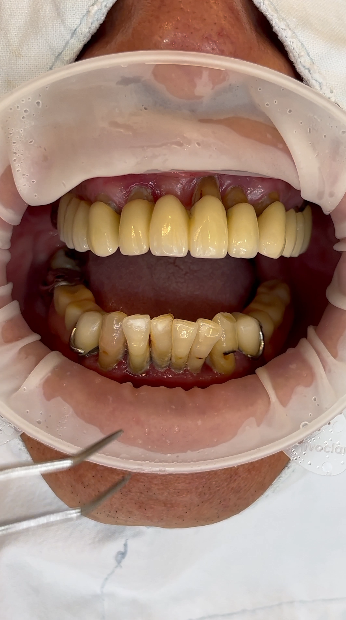

전체적으로 치아가 좋지 않은 분이 전체적으로 치아를 뽑고 치료를 하고자 하셨어요. 환자의 치료전 상태는 전체적으로 치주염(잇몸질환)이 심해 치조골(잇몸뼈)이 모두 녹아버려 치아들이 많이 움직이고 잇몸이 많이 내려간 상태였습니다. 아래에는 부분틀니도 착용하고 있었습니다. 아래 파노라마 엑스레이에서 볼 수 있듯이 살릴 만한 치아가 없어 모두 발치를 하고 전체임플란트로 치료하기로 했어요.

전체적으로 이렇게 치아상태가 좋지 않을 경우에는 치료를 시작하기 전에 걱정이 많을 수 밖에 없지요. 거의 모든 치아를 뽑아야 할 것 같은데 치아 없이 지내는 시간이 걱정되는 분들도 있고, 비용이 많이 들까바 걱정하는 경우, 아플까바 걱정하는 경우도 있어요.